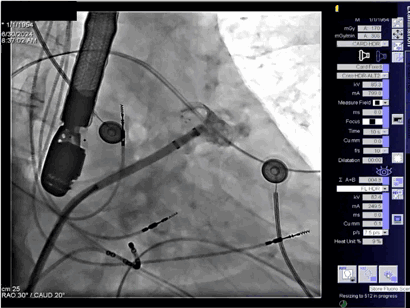

▲固定盘释放形态良好

推送封堵器的固定盘到达预定位置,固定盘打开良好,mark点与封堵器腰部显影点基本位于同一条直线上,未影响回旋支。